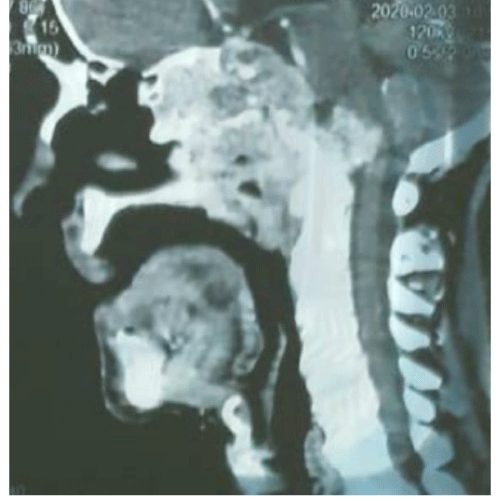

Nerves Paralysises Associated to Nasal Obstruction : What Is Your Diagnosis ??

Ilham Rkain1,2*, Safaa Touihmi1 and Hicham mimouni3

A 60 year old man presented with complaints of nasal obstruction (left side), smell disorder , headache and neuralgia on the left side of his face for 2 years, ptosis and diplopia followed by reduction vision of the left side...